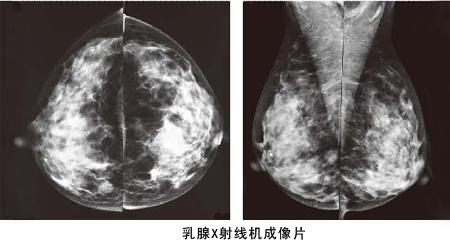

乳腺鉬靶X線片不同于普通X線片,普通X線片對乳房中正常組織與腫塊影的鑒別能力很差,而乳腺鉬靶X線片能精細地記錄下不同穿透能力的軟組織留下的X線影像,特別是能捕捉到對乳腺癌具有診斷意義的微小鈣化灶。臨床應用證實,它能發(fā)現(xiàn)小于5mm的癌腫,可以至少比臨床提前1年發(fā)現(xiàn)乳腺癌。

乳腺鉬鈀檢查系統(tǒng)成像

乳腺鉬鈀檢查系統(tǒng)具有乳腺斷層攝影技術(shù)、乳腺對比增強技術(shù)、立體定位活檢技術(shù),合三為一,貫穿乳腺篩查、診斷、治療全路徑,更準確、清晰的成像,更早發(fā)現(xiàn)乳腺癌微小病變,為乳腺癌早期發(fā)現(xiàn)、早期診斷以及治療和術(shù)后監(jiān)控全流程帶來完整的解決方案,被作為目前全球范圍內(nèi)乳腺影像檢查的“金標準”。